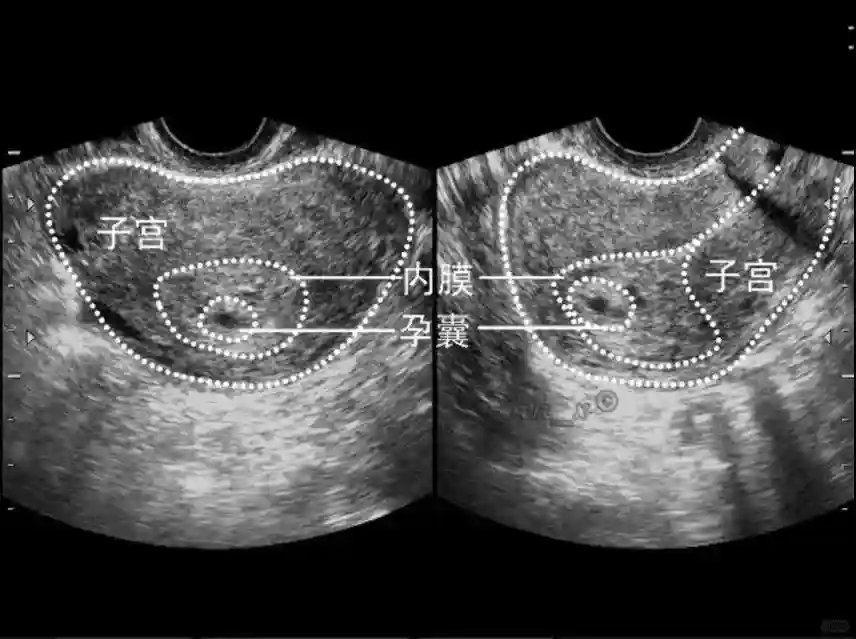

1️⃣妊娠囊:早期妊娠囊:正常妊娠囊位于宫腔上段,表现为宫腔内圆形或椭圆形的无回声区,周边为完整的、厚度均匀的强回声环,强回声环厚度≥2mm,强回声是妊娠绒毛的回声,随着妊娠囊的增大,形成特征性的“双环征” ,10周以后消失。正常的妊娠囊增长速度是平均 1 mm /d。

2️⃣卵黄囊:是妊娠囊内第一个解剖结构,直径<7mm。表现为小环状,中央为无回声,囊壁薄,内透声好。卵黄囊位于胚胎旁胚外体腔内。卵黄囊通常在孕5-6周时出现,5-10周稳步增长,一般不超过7mm,至12周消失。妊娠囊的大小与卵黄囊之间有一定关系,妊娠囊平均直径> 8 mm 时,经阴道超声均应显示卵黄囊,妊娠囊平均直径> 18 mm 时,经腹超声均应显示卵黄囊。